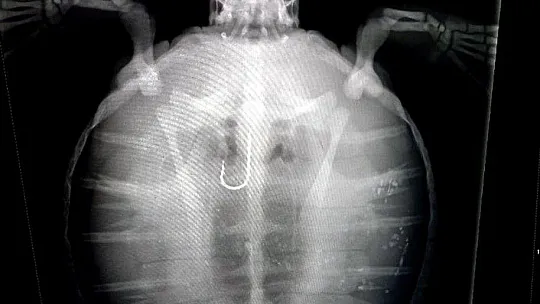

Bölgede su sporları işleten ekip tarafından bulunan ve kurtarılan küçük yeşil deniz kaplumbağası (Chelonia mydas) Deniz Kaplumbağaları Araştırma Kurtarma ve Rehabilitasyon Merkezi (DEKAMER)’e teslim edildi.

DEKAMER ekibi tarafından kurtarılan yeşil deniz kaplumbağasının ilk kontrolleri yapıldıktan sonra merkeze getirildi. Misina ile birlikte olta iğnesi yuttuğu tespit edilen ve Berrak adı verilen henüz 3 kilogram ağırlığındaki kaplumbağa gözlem altında tutuluyor.